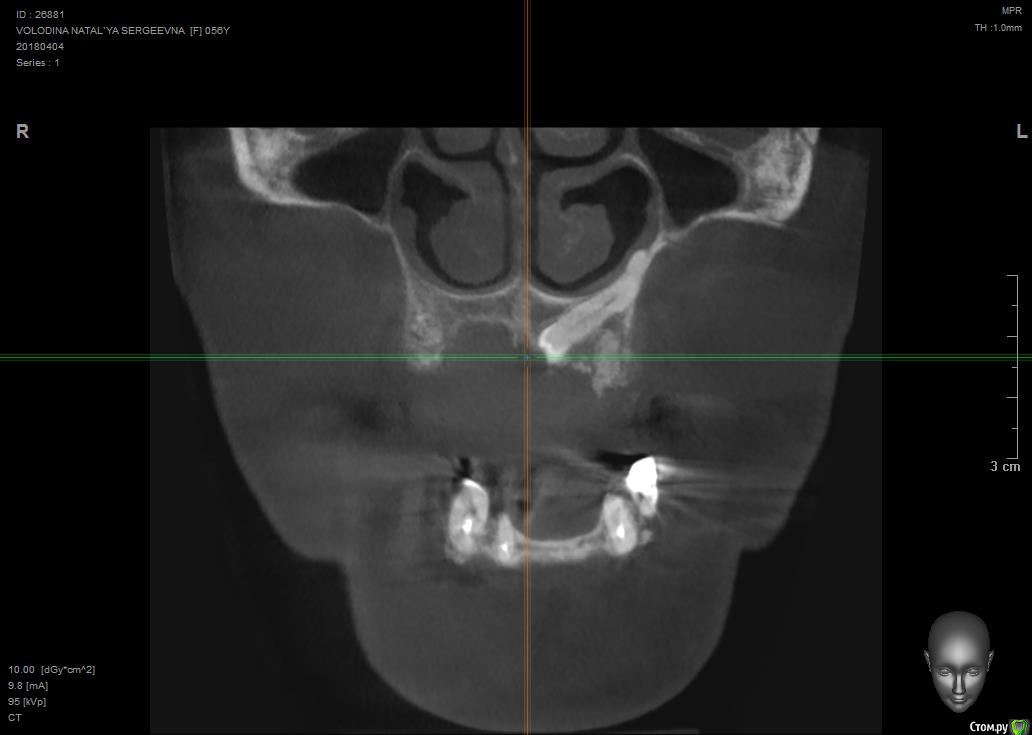

Павел7809 Опубликовано 9 апреля, 2018 Поделиться Опубликовано 9 апреля, 2018 Собственно ситуация такая. Предстоит каким то образом удалить ретенированный клык. Находится в небе, да и еще кривым апексом который торчит в носу. Полгода назад этому же пациенту почти такой же клык я удалил, но там как то все проще было по топографии. Собственно , господа, как и чем? Возможны ли какие то кровотечения носовые и тд. Кто сталкивался? Может как то распилить его со стороны щеки пополам и вытащить.. Ссылка на комментарий

Павел7809 Опубликовано 9 апреля, 2018 Автор Поделиться Опубликовано 9 апреля, 2018 Может так получше. Орто нет... Ссылка на комментарий

Павел7809 Опубликовано 9 апреля, 2018 Автор Поделиться Опубликовано 9 апреля, 2018 Так все тоже самое:Анестезия.Разрез.Декоронация.Удаление корня.Кюретаж.Швы.В нос провалитесь - плохо, но не страшно, будет кровать, тампонада носового хода.Я ведь правильно понимаю - сначала надо будет отрезать крючек со стороны щеки, сделав к нему окошко на уровне апексов 6 ки а потом удалить все остальное через небный доступ? Ссылка на комментарий

Борис80 Опубликовано 10 апреля, 2018 Поделиться Опубликовано 10 апреля, 2018 я бы вестибулярно делал, окно в области коронковой части, чуть апикальнее может, коронку отпилил, корень вывихнул Ссылка на комментарий